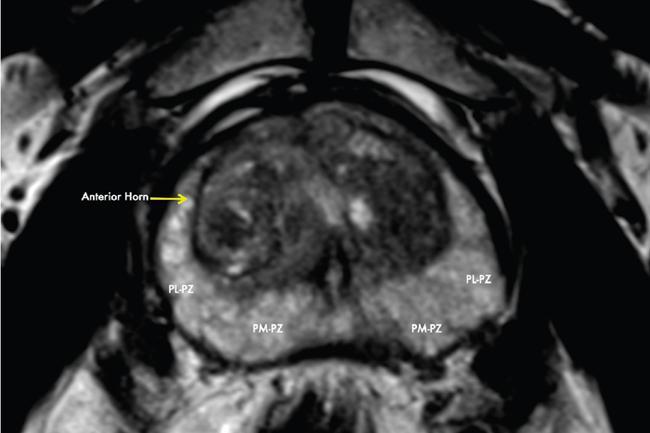

Karthik Ganesan, Disha Lokhandwala, Ujjwal Bhure, Jay Mehta Morphogenesis of the male genitourinary system is governed by the coherent interaction of three units, namely the Wolffian duct, urogenital sinus and foetal gonads. The Wolffian ducts are the embryonic precursors of the male internal genitalia, arising in the anterior intermediate mesoderm at 4 weeks of gestation. They elongate as a cord of cells that caudally extend to the urogenital sinus. Between 5 and 8 weeks of gestation, the urorectal septum divides the cloaca into a ventral compartment, which forms the urogenital sinus, and a dorsal compartment, which forms the rectum. The gonads form as epithelial thickenings on the ventromedial surface of the mesonephros and produce testosterone at 8 weeks of gestation, reaching a peak at 10–15 weeks. Under the effect of testosterone produced by the foetal testis, the prostate anlage forms at the tenth week of gestation. Precursor of the anlage begins with proliferation of solid epithelial buds from the epithelium of the urogenital septum into the adjoining mesenchyme in response to interaction of 5α-dihydrotestosterone with mesenchymal androgen receptors. As growth progresses, solid cords of epithelial cells are formed, growing into the mesenchyme in a specific three-dimensional arrangement (establishes the lobar divisions of the prostate gland). These solid cords develop a central lumen at birth and are lined by a layer of flat basal epithelium and a luminal layer of tall columnar secretory epithelium. Mesenchymal component forms the stroma, which has a large proportion of smooth muscle. Postnatally, the epithelial cords continue to arborize till puberty without any change in volume or glandular architecture. Although the foetal prostate has been described to have a histologically distinct peripheral zone (PZ) as early as 12 weeks of gestation, the mature zonal anatomy develops in concordance with the androgen surge at puberty. The most commonly utilized ultrasonographic technique for the evaluation of the prostate is via a suprapubic approach. The abdominal transducers used in this approach are relatively low frequency and while it offers the advantage of greater depth of penetration without intracavitary probe insertion; however, it does not depict the zonal anatomy and its chief application lies in volume estimation. Hence, transrectal ultrasonography (TRUS) completely outweighs the transabdominal approach in terms of depicting zonal anatomy, visualizing and localizing small lesions, demonstrating vascularity and performing biopsies. TRUS is performed using high frequency transducers (5–7.5 MHz) to optimize soft tissue resolution. An enema is administered 1 h prior to the examination to clear the field of insonation. Patient is positioned in left lateral decubitus, with knees bent toward the chest and ideally a digital rectal examination (DRE) is conducted prior to probe insertion. The transducer is first draped with a sterile barrier and lubricated, After insertion, the barrier is filled with 40–50 cc of water, making sure that no air enters. On completion, water is aspirated and the probe is withdrawn. The gland is initially scanned in the axial plane from the base to the apex, beginning at the level of the seminal vesicles, and the probe is gradually withdrawn to view the entire glandular parenchyma in axial sections up to its caudal aspect. This approach allows a cursory evaluation of glandular symmetry as both halves of the prostate can be evaluated simultaneously. Subsequently, sagittal views are acquired by rotating the probe across the transverse span of the gland, demonstrating the seminal vesicles, midline gland (visualizing both the apex and the base), with sequential scanning up to the contralateral margin of the gland. Sonographically, the prostatic capsule is seen as a smooth well-delineated, hyperechoic structure. With the newer ultrasound systems, the zonal anatomy can be delineated by TRUS; PZ appears echogenic relative to the central zone (CZ) and the transition zone (TZ), which are hypoechoic in juxtaposition (Fig. 11.12.1). Anterolaterally, the preprostatic venous plexuses are seen as anechoic tubular structures with intervening echogenic preprostatic fatty tissue. Glandular volume is estimated using an ellipsoid formula by obtaining the maximum anteroposterior, superoinferior and transverse dimensions and multiplying their product by π/6. Colour Doppler imaging is utilized to illustrate vascularity, as majority of the normal prostatic tissue (excluding the neurovascular bundles [NVBs] and pericapsular and periurethral regions) has symmetrical but sparse flow and an increased microvessel density raises the suspicion of prostatic carcinoma. However, the appearances of prostatic carcinoma can be variable on colour Doppler imaging, ranging from focal increase in vascularity around a nodule to an asymmetric increase in size and number of vessels on the affected side and conventional Doppler has found to elevate specificity by about 5%–10%. Additionally, Doppler imaging has also demonstrated some utility in distinguishing fibrotic tissue from local recurrence. However, vessels supplying cancerous tissue are of the order of 10–50 μm, which is well below the 1-mm resolution limit of conventional Doppler techniques. Contrast-enhanced colour Doppler imaging overcomes this limitation and facilitates imaging of microvessels, using intravenously administered microbubbles (less than 10 μm diameter) of an inert gas (sulphur hexafluoride) with a lipid or galactose shell, allowing quantification of blood flow in the cancerous microvessels. Additionally, these microbubbles act as vascular tracers and by monitoring the passage of a bolus injection through the tissue of interest, time–intensity curves are created. This permits the formulation of functional indices, including bolus arrival time, time to peak intensity, area under the curve and wash-in/wash-out curves. These indices can further extrapolate functional images, on a pixel-by-pixel basis, overlaid on grey-scale images. Quantitative methods to demonstrate perfusion are based on the destruction of microbubbles by high-power ultrasound pulses, and then observing the rate of microbubble replenishment in the field of interest to calculate flow rate. Halpern et al. utilized contrast-enhanced ultrasound and intermittent harmonic imaging with power Doppler, and exhibited an increment in sensitivity from 38% to 65% with a specificity of 80% in prostate cancer detection. Cadence contrast pulse sequencing (CPS) is a low-power multipulse imaging technique utilizing pulses with variable amplitudes and phases followed by a summation of the resulting echoes, permitting tissue suppression, allowing detection of even a small amount of contrast agents retained in the tissues. Real time elastosonography evaluates and quantifies tissue stiffness (Young’s modulus) by measuring strain under an applied stress (transducer compression) and maps areas of variable stiffness in colour-coded and grey-scale images simultaneously and shows potential in improving prostatic carcinoma detection. In a study comparing elastography and T2-weighted (T2-w) endorectal magnetic resonance imaging (MRI), similar sensitivity rates and negative predictive values (NPVs) were attained in the detection of prostatic carcinoma. Prostate gland is an inverted cone-shaped subperitoneal retropubic gland, with its base located rostrally and apex located caudally. The base is attached to the bladder neck and the apex sits on the urogenital diaphragm and abuts the medial surface of the levator ani muscles, namely the pubourethralis portion, which is separated from the inferolateral surfaces of the gland on either side by the prostatic venous plexus. Normal prostate gland measures approximately 4 × 3 × 3 cm, 15–20 g in weight, with a median volume of 11.5 mL (range, 1.6–20.6) in patients between 21 and 25 years and a median volume of 39.6 mL (range, 13–169.8) in patients between 38 and 83 years. The first comprehensive publication describing the anatomical subdivision of the prostate gland was in 1912 by Lowsley, based entirely on the embryonic glandular morphology at a series of gestational age groups. The budding prostatic ducts were seen to proliferate in five distinct clusters from the primitive urogenital sinus, which formed the basis of its lobar subdivision. It was divided into a ventral lobe (anterior to the urethra), two lateral lobes (lateral to the ejaculatory ducts), a posterior lobe (between the ejaculatory ducts) and a middle lobe (above the ejaculatory ducts). This classification had several shortcomings, the foremost being inclusion of only the embryonic prostate during its conception. Frank highlighted these aspects in 1953 and stated that no definite lobar boundaries exist in the adult prostate and further criticized the exclusion of periurethral glands (inner gland), identifying them as the sole site of origin of benign prostatic hyperplasia (BPH). The chief drawback of all research prior to 1968 was the lack of a concrete histological basis to support the seemingly arbitrary subdivision. McNeal was the first to ascertain histological heterogeneity within the glandular tissue and used it as the basis of his well-acclaimed prostatic zonal classification. The zonal anatomy of the prostate gland conceived by McNeal divided the gland into four distinct zones, namely the TZ, PZ, anterior fibromuscular zone (AFMZ) and the CZ (Fig. 11.12.2). McNeal used the plane of the distal urethra to describe the zonal relationships and divide the gland broadly into three parts, namely the base, midgland and the apex (Fig. 11.12.3). The improved understanding of the prostate anatomy coincided with the development of MRI in the late 1980s, which could depict the zonal anatomy, unlike ultrasonography (USG) or computed tomography (CT). Patterns of ductal growth and radiation from the prostatic urethra form the basis of the zonal anatomy of the gland. Ducts arising from the proximal urethral segment grow towards the urinary bladder. Tiny ducts which are confined by the preprostatic sphincter form the small periurethral gland, whereas ducts which develop distal to the lower border of the preprostatic sphincter extend laterally and then anteromedially to form the TZ. Ducts arising from the verumontanum in the vicinity of the ejaculatory duct orifices and are directed towards the base along the course of the ejaculatory ducts form the CZ, whereas ducts which arise from the lateral recess of the posterior urethral wall of the verumontanum and distal urethra radiate laterally to form the PZ and rostrally posterior to the CZ at the base of the gland. PZ is the dominant glandular component of the prostate gland comprising approximately 70% of the glandular tissue. On T2-w images, the normal PZ has a high T2 signal intensity (SI), owing to the abundant ductal and acinar elements with sparsely interwoven smooth muscle, and can broadly divided into three sections as per the sector map in Prostate Imaging Reporting and Data System Version 2.1 (PI-RADS v2.1), namely posterior medial, posterior lateral and anterior sections (Fig. 11.12.4). At the apex, the anterior sections have a horn-like morphology, curving anteromedially, to nearly encircle the urethra and abut the AFMZ. At the midgland level, the PZ comprises the posterior, both lateral and the anterolateral parts of the gland. At the base, the PZ is located posterior and superior to the CZ and TZ. CZ is an ovoid-shaped structure at the base of the gland, comprising approximately 25% of the glandular tissue, with its apex located at the verumontanum, surrounding the ejaculatory ducts. Beyond age 35, volume of the CZ starts to gradually diminish, as well as the CZ is compressed by the enlarged TZ. In the initial MR studies of prostate, the CZ could not be easily delineated from the TZ. Vargas et al. demonstrated in a population with a mean age of 60 years undergoing MR for prostate cancer assessment, the CZ was visible in 81%–84% of patients. Hansford et al. identified the CZ in 92%–93% of patients on T2-w images and 78%–88% of patients on apparent diffusion coefficient (ADC) maps. Histologically, substantial differences exist between the CZ and PZ, which reflect in the differential appearance on T2-w imaging. These differences are probably attributable to the differential origin, as the CZ is derived from the Wolffian duct, and the PZ and TZ are derived from the urogenital sinus. In the CZ, the acini appear larger and more irregular, with numerous epithelial covered ridges or septa project from the walls of the acini into the lumen, forming a characteristic Roman bridge architecture and intraglandular lacuna, with a prominent basal layer, crowded epithelial cells with granular eosinophilic cytoplasm, decreased luminal fluid and compact stroma. PI-RADS v2 has discouraged the use of the term central gland, as it is not reflective of zonal anatomy or reported on pathologic specimens. CZ demonstrates homogeneously low signal on the T2-w images and ADC maps and can, therefore, mimic prostate cancers. CZ is best identified on the coronal plane T2-w images paralleling the plane of the distal urethra, and appears as a symmetric paramedic paired structures surrounding the ejaculatory ducts from the base of the gland to the verumontanum (Fig. 11.12.5). TZ comprises approximately 5% of the glandular tissue of the prostate. On T2-w images, the TZ normally appears as a homogeneously hypointense structure surrounding the proximal urethra at the base and the midgland level; however, it can also demonstrate inconsistent SI, depending on the relative proportion of glandular and stromal elements (Fig. 11.12.6). Glandular hyperplasia produces higher SI (dominance of acinar elements and secretions), while stromal hyperplasia exhibits lower SI (dominance of muscular and fibrous elements). The TZ is easily demarcated from the PZ by a thick homogeneously low T2 signal surgical capsule, which becomes pronounced in BPH. With increasing age, the TZ demonstrates variegated signal on the T2-w images and ADC maps, due to differential growth of the stromal and glandular elements. AFMZ is a nonglandular muscular tissue that drapes the anterior surface of the gland, superiorly blending into the smooth muscles of the bladder neck and inferiorly extending to the prostatic urethra at the glandular apex. AFMZ is comprised of smooth muscles, which blends with the smooth muscle fibres surrounding the urethra, and rostrally merges with the bladder neck and preprostatic sphincter. High smooth muscle content of the AFMZ is responsible for the MR signature, where in it appears markedly hypointense on the T2-w images and ADC maps, and hypoenhances on the multiphase contrast series (Fig. 11.12.7). With the advancing age, temporal reduction in the size of the AFMZ is noted due to the compressive effects of the BPH. Capsule surrounds the prostate gland, anteriorly merging with the AFMZ anteriorly. Two discrete defects are identified in the prostate capsule, at the base of gland where the ejaculatory ducts enter the prostate and at the apex where in the stroma blends with the sphincter. The capsule is perforated along the anterolateral aspect by multiple vessels and nerves. The capsule appears as a thin dark rim surrounding the gland on the T2-w images and may reveal delayed enhancement on the postcontrast images (Fig. 11.12.8). Primary goal of radical prostatectomy (RP) is to achieve oncologic efficacy, both in terms of short-term and long-term clinical outcomes. However, as the majority of prostate cancers have an indolent clinical course, preservation of function in terms of continence and potency is equally important, and the key to this is a keen understanding of the fascial anatomy and neuroanatomy of the prostate gland. Fascial anatomy of the prostate gland is anatomically complex and poorly understood, and a thorough understanding of the interfacial planes is crucial to avoid mechanical or thermal injury to the NVBs. Periprostatic fascia comprises of a condensation of layers of connective tissue that encapsulate the gland and suspend it from anterior pelvic wall via puboprostatic ligaments. Laterally, the visceral and parietal endopelvic fascial layers fuse to form the fascial tendinous arch. Periprostatic fascia covers the prostate gland and capsule, comprises of two fascial layers, including an inner layer (prostatic fascia) and an outer layer (levator ani fascia), with thin interfascial planes separating these fascia from one another and the prostate capsule. Posteriorly, a continuous fascial layer known as Denonvilliers’ fascia covers the prostate and seminal vesicles. Distribution of periprostatic nerves is highly variable, with growing evidence of nerves both along the dorsolateral and ventrolateral surfaces of the prostate gland. Most of the periprostatic nerves are found posterolaterally; however, a significant portion of the nerves are located ventrally as seen by Eichelberg et al. (21.5%–28.5%) and Lee et al. (19.9%–22.8%). Although anatomic studies have confirmed the presence of ventrolateral periprostatic nerves, the exact clinical importance and functionality of these nerve fibres has not been proven. The cavernous nerves are situated posterolaterally and are the basis of nerve-sparing RP procedure proposed by Walsh and Donker. Unlike the initial theory of Walsh and Donker, few papers have proposed that the nerves are diffusely scattered along the surface of the gland in the form of a curtain or spray-like arrangement without clear bundle formation. Kourambas et al. assessed the precise relationship of the NVBs and cavernous nerves to Denonvilliers’ fascia and proposed that the nerves were not restricted posterolaterally, but were rather diffusely scattered within the fascia extending up to the midline (Lunacek et al., Takenaka et al.). On the basis of more diffuse arrangement of the periprostatic nerves, surgical techniques have been modified, resulting in a more anterior dissection called the ‘curtain dissection technique’ or alternatively a ‘superveil’ technique to preserve the NVBs within the lateral prostatic fascia. The NVB lies within areolar connective tissue surrounding the gland, which separates the capsule from the periprostatic fascia and provides a plane of dissection during nerve-sparing prostatectomy. Prostate gland is supplied and drained by periprostatic vessels, which also supply and drain the penis. Arterial supply of the gland is highly variable and is typically from branches of the internal pudendal artery, which course inferior to the gland prior to supplying the penile cavernosal tissue. Off late, these vessels have gained prominence in radiation-induced erectile dysfunction (ED) (potential vasculopathy), which have led to the development of newer vessel-sparing radiotherapy techniques. Further, with the advent of prostate arterial embolization in benign prostatic hypertrophy (BPH), the vascular supply of the gland is becoming increasingly vital to understand. Gland drains into the obturator, internal iliac, external iliac, common iliac and presacral lymph nodes. Dorsal venous complex is identified immediately ventral to the gland and also drains the penis. Periprostatic nodes are uncommon, are usually discovered near the base of the gland, and are only occasionally seen on MRI. Urethra is the principal anatomic reference point in the prostate gland. Urethra can be divided into a proximal segment and a distal segment, the point of differentiation being located at the verumontanum wherein the urethra makes an approximately 35-degree angulation. The angulation is highly variable and is further affected by the growth of the TZ. On MRI, the distal segment is more conspicuous vis-à-vis the proximal segment and appears a hyperintense core surrounded by a low signal rim on T2-w images. Preprostatic sphincter encases the proximal urethra from the base of the gland to the base of the verumontanum and merges with the AFMZ anteriorly. Verumontanum appears hyperintense on the T2-w images, lies within the distal urethral segment, beyond which the distal urethral segment is partially encircled by striated muscles which blend with the external sphincter beyond the apex of the gland. External sphincter is located distal to the apex is incomplete posteriorly and is anchored into the PZ and surrounds the membranous urethra. Damage to the external sphincter during RP or transurethral resection of the prostate (TURP) may lead to urinary incontinence. Seminal vesicles are paired structures identified posterosuperior to the base of the prostate gland, which appear as convoluted fluid-filled structures. Due to the high fluid content within the normal seminal vesicles, these structures appear as paired structures with intermediate signal walls surrounding a hyperintense core on T2-w images (Fig. 11.12.9). Vas deferens are paired structures located rostral to the base of the gland and anteromedial to the seminal vesicles and appear as cord-like structures with variable signal on the T2-w images. Duct of the seminal vesicle and vas deferens unite in the posterior aspect of the base of the gland to form the ejaculatory duct, which courses caudally to the verumontanum along the plane of the distal urethra, and drain into the orifices in the midconvexity of the verumontanum. Prostate-specific antigen (PSA) is a serine protease, secreted by epithelial cells of the prostate gland and has been found in normal, benign and malignant prostatic tissues. Traces of PSA have also been isolated from endometrial tissue, breast tissue, adrenal neoplasms and renal cell carcinomas; however, for all clinical purposes, PSA is considered as an organ-specific biomarker. Papsidero first demonstrated and quantified serum PSA, which steered the epoch of prostate cancer screening and early detection of prostatic carcinoma. Subsequent studies showed that PSA screening often led to overdiagnosis of low-grade prostate cancers, with no survival difference between the PSA screened and nonscreened groups. Additionally, PSA levels were found to be elevated in a spectrum of prostatic pathologies apart from carcinoma, including prostatitis and benign hyperplasia. The likelihood of overdiagnosis coupled with the lack of specificity set grounds for the longstanding PSA controversy. Did the benefits of screening outweigh the risks of overtreatment? To elevate the specificity of serum PSA testing, a plethora of indices were devised, including free PSA and total PSA, free-to-total PSA (f/t PSA) ratio, age-specific PSA, PSA velocity (PSA-V) and PSA density (PSAD). Serum PSA exists in three forms; the major form (approximately 75%) is bound to alpha-1-antichymotrypsin, followed by free PSA (constituting 5%–50% of serum PSA). The third form (PSA bound to alpha-2-macroglobulin) is not clinically relevant and cannot be detected by any commercial test. A study by Stenman et al. established that a higher proportion of bound PSA and hence a lower ratio of f/t PSA is associated with prostate cancer. Conversely, free PSA can be utilized during follow-up for men with an initial negative biopsy result, wherein declining free PSA with a persistently elevated total PSA would raise suspicion of a neoplastic aetiology. As per the ACS guidelines (Table 11.12.1) for early detection of prostate cancer, men with a 10-year life expectancy or higher should have the opportunity to make an informed (regarding benefits, risks and uncertainties associated with PSA screening) decision for serum PSA testing, with or without DRE. For those who choose to undergo PSA screening, subsequent screening interval is determined on the basis of baseline PSA value. For values below 2.5 ng/mL, screening interval can be extended to 2 years and for PSA between 2.5 ng/mL and 4 ng/mL, an individualized approach is adopted following risk assessment to recommend either further referral or screening on a yearly basis. A PSA level of 4 ng/mL or higher warrants referral for further evaluation or biopsy, for men at average risk for prostate cancer. Although age-specific PSA (Table 11.12.2) is not a component of the ACS guidelines, it is considered as a beneficial parameter in determining the need for biopsy. As there is an expected rise in PSA values with age, setting a lower cut-off value for younger men would increase the sensitivity of detecting organ confined cancers and a higher value in older men would increase specificity. aThere is no proven rationale for using a single PSA-V threshold value. PSA screening guidelines for treated localized prostate cancers are variable and the definition of biochemical (PSA) recurrence remains debatable. Due to this inconsistency, the Prostate Cancer Guidelines Update Panel recommended a standard definition for biochemical recurrence (BCR) after RP and set a cut-off serum PSA (acquired between 6 weeks and 3 months of surgery) of 0.2 ng/mL or greater, along with a second confirmatory PSA. While there is a significant fall in PSA values after RP and a single raised PSA is sufficient to raise suspicion of recurrence, postradiotherapy recurrence requires a rising trend rather than a single cut-off value. The ASTRO Consensus Panel defined postradiotherapy prostate cancer recurrence as three consecutive raises in PSA values after a baseline has been reached. A hiatus in this definition was that no specific time interval between consecutive increases in PSA was determined. In addition to its utility as a screening tool, PSA is also a good prognosticator when used in conjunction with biopsy Gleason score and clinical T-stage, and several pretreatment prostate cancer risk stratification systems are based on these indices. D’Amico et al. proposed a three-group risk stratification system in 1998, which categorized nonmetastatic (M0) carcinomas as low risk, intermediate risk and high risk. Low-risk prostate cancer was defined as 1992 AJCC T1/T2a, PSA ≤10 ng/mL and Gleason score ≤6. Intermediate-risk prostate cancer was defined as 1992 AJCC T2b, and/or PSA 10–20 ng/mL and/or Gleason 7 disease. High-risk disease included any one of the following: 1992 AJCC ≥T2c, PSA >20 ng/mL or Gleason 8–10 disease. In 2001, the GUROC published the results of a consensus meeting which categorized the groups as follows: low risk – 1997 AJCC T1–T2a, PSA ≤10 ng/mL and Gleason ≤6; intermediate risk – 1997 AJCC T1–T2, PSA ≤20 ng/mL and Gleason ≤7 not otherwise low risk and high risk – 1997 AJCC T3–T4 or PSA >20 ng/mL or Gleason 8–10. In due course, newer classification systems have been developed (Table 11.12.3), including the National Comprehensive Cancer Network (NCCN, USA), National Institute for Health and Clinical Excellence (NICE, UK), European Society of Medical Oncology (ESMO), American Urological Association (AUA) and the European Association of Urology (EAU). The NCCN guidelines also incorporate very low-risk (T1c, and Gleason score ≤6, PSA ≤10 ng/mL, <3 positive biopsy cores each ≤50% involved and PSAD of <0.15 ng/mL/g) and very high-risk (T3b–T4) categories. AUA, American Urological Association; EAU, European Association of Urology; GUROC, Genitourinary Radiation Oncologists of Canada; NICE, National Institute for Health and Clinical Excellence; CAPSURE, Cancer of the Prostate Strategic Urologic Research Endeavour; NCCN, National Comprehensive Cancer Network; ESMO, European Association of Urology; T, T-stage; GS, Gleason score; PSA, prostate-specific antigen. Note: Use of the 1997 TNM staging system (T2a one lobe involvement, T2b two lobes involvement, no T2c category). PSA, DRE and TRUS form the diagnostic triad for prostatic carcinoma. It has been well established that manipulations of the prostate gland, including prostatic massage, cystoscopy and perineal biopsy cause a potential increase in serum PSA levels. This raised the question of TRUS affecting PSA levels and it was found to cause a very small rise in PSA only in patients with prostatitis. The effect of DRE on serum PSA levels is also controversial, while some studies found a transient increase in PSA, others found no significant rise in PSA levels after DRE. Therefore, it is advisable to obtain blood samples for PSA testing either prior to DRE and TRUS or after at least 7 days. PSA-V refers to the change in PSA over time using serial measurements. Ideally, at least three consecutive measurements over at least 18–24 months should be used. Carter et al. first defined PSA-V and found that a value of 0.75 ng/mL per year or greater was indicative of carcinoma with a high sensitivity and specificity. Consequently, several studies disproved a definite relationship between PSA-V and prostate cancer, stating that there was no rationale behind a single threshold value for PSA-V. Further, it was found that calculating PSA-V was arduous and while elevated PSA values on serial examinations should raise alarm, there was no added benefit of formally calculating PSA-V. As per NCCN guidelines, the PSA-V cut-off should be based on the initial PSA value with a PSA-V of 0.35 ng/mL/y, when the PSA is ≤2.5 ng/mL and 0.75 ng/mL/y, when the PSA is 4–10 ng/mL PSAD was developed in order to correlate prostate volume and PSA values. The basis of PSAD was that cancer cells produce more PSA per unit volume than normal cells. It is calculated as PSA value divided by the prostate volume as determined by TRUS. This reliance on TRUS leads to interobserver variability and hence PSAD values would differ with the performing sonologist. The chief utility of PSAD is in the diagnostic grey zone of PSA values between 4 and 10 ng/mL and the most commonly used cut-off value is 0.15 ng/mL/cc. However, more recent studies have shown that a value of 0.08 ng/mL/cc has an NPV of 95% in predicting prostate cancer. Additionally, PSAD in conjunction with MRI (PI-RADS score) has proved to be a reliable prognosticator for Gleason score upgrading. The most significant application being avoiding unnecessary biopsies as PI-RADS scores of 1–3 along with PSAD values <0.15 ng/mL/cc showed no Gleason score upgrading on repeat biopsies. In summary, most guidelines recommend shared decision-making for screening of prostate cancer. Limited testing should be conducted in men with low PSA values and a lower life expectancy. The aim should be to overcome challenges posed by the inherent nonspecific nature of serum PSA and reduce superfluous testing, unwarranted biopsies and overdiagnosis. Reliance on parameters like PSA-V that do not have a proven scientific basis is avoidable. Whereas applications of PSA like PSAD along with MRI can greatly reduce patient burden by avoiding follow-up biopsies. Lastly, PSA has no role in assignment of a PI-RADS category, which is based on multiparametric MRI (mpMRI) findings alone. Several ‘novel biomarkers’ are now being developed which are more specific in detecting high-grade prostatic carcinomas. Other human kallikrein proteins have been identified, as prostate cancer biomarkers, of which, human kallikrein 2 (hK2) has shown a high specificity. While hK2 and PSA have an overlapping primary structure, malignant cells express hK2 to a higher degree than benign epithelial cells, particularly in aggressive cancers. Engrailed-2 (EN2) is an HOX gene family transcription factor seen exclusively in malignant prostate tissue, with a reported sensitivity and specificity of 66% and 88%, respectively. Annexin A3 is a calcium-binding protein measured in urine samples following prostatic massage, potentially reducing unnecessary biopsy in men with a PSA of 2–10 ng/mL. However, extensive prospective evaluation of these biomarkers is necessary to replace PSA testing in clinical practice. Positron emission tomography (PET)/CT has evolved over the last two decades to make a paradigm shift in the field of imaging, moving from morphological imaging to molecular level and completely changing the approach to how we view the disease. Though the main workhorse tracer in the field of PET/CT is 18-fluorine-fluorodeoxyglucose (18F-FDG), it has limitations with regard to prostate cancer, especially in indolent or well-differentiated ones. However, that void has been filled up by the new kid on the block and that is prostate-specific membrane antigen (PSMA)-based radiotracer. PSMA is a type II transmembrane protein with intracellular (19 amino acids), transmembrane (24 amino acids) and extracellular (707 amino acids) domains, which functions biochemically as a glutamate carboxypeptidase. After a ligand binds to PSMA, internalization occurs and it is either retained in lysosomal compartments or released into the cytoplasm. PSMA expression and localization in the normal human prostate is associated with cytoplasm and apical side of the epithelium surrounding prostatic ducts but not basal epithelium and neuroendocrine or stromal cells. Neoplastic transformation of prostate tissue results in the transfer of PSMA from the apical membrane to the luminal surface of the ducts. PSMA is an ideal target for molecular imaging of prostate cancer as its expression is significantly upregulated in prostatic carcinoma cells compared to benign prostatic tissue, in density (100 to 1000 times) as well as activity (8 to 10 times). PSMA expression increases with increase in Gleason score, stage and grade of tumour, with further increased expression with transition to androgen-independent/castration-resistant prostate cancer. PSMA-binding analogues, because of their high sensitivity and specificity, possess precise imaging characteristics required for critical decisions in the management of prostate cancer (PCa). The most commonly used PSMA radiotracer is 68Gallium-PSMA-11, followed by 18F-PSMA. The availability of 18F-labelled PSMA radiopharmaceutical has helped to advance the reach of PSMA PET imaging to wider locations owing to higher available amount of the radiotracer due to its production from a cyclotron, compared to 68Ga-PSMA which is eluted from individual in-house generator. Additional benefit is accrued with excellent image quality owing to optimized radiotracer doses, higher imaging statistics and favourable decay properties of 18F radioisotope. The normal physiological biodistribution of PSMA-based radiotracers is seen in lacrimal and salivary glands, liver, spleen, kidneys and intestine. Physiological activity is also seen in celiac and cervicothoracic ganglia. Unbound PSMA radiotracer is excreted by the kidneys into the urinary bladder. PSMA PET/CT has established roles of varying degrees in the imaging of different aspects of prostate cancer including primary diagnosis, staging, BCR after primary prostate cancer treatment (prostatectomy), identification and significance of oligometastasis, restaging and treatment response assessment and monitoring. PSMA PET/CT is useful at the stage of diagnosis in that subset of patients with tumour-negative biopsy samples, by contributing the useful molecular information to mpMRI, helping to precisely delineate suspicious lesions for targeted biopsies. In intermediate-risk to high-risk primary prostate cancer patients, PSMA-based imaging has shown improvement in detection of metastatic disease compared to the CT and mpMRI, which has led to reduced demand and dependence on additional cross-sectional imaging or bone scintigraphy. Furthermore, PSMA PET/CT has also established its clear advantage over conventional imaging in patients with biochemically recurrent prostate cancer with improved and increased detection of metastatic sites even at low serum PSA values. As it happens in cancer, biopsy is the standard of diagnosis and likewise in PCa, it is the multicore biopsy, which is the gold standard. However, because of its size, location, approach and sensitive and delicate nature, yield and accuracy can often be restricted, especially in inexperienced hands. The diagnostic yield of biopsy can go down as low as 40% and false negative (FN) rate can climb as high as 25%–30%. PSMA overexpression follows high-grade PCa cells and increases with Gleason score. In normal prostate tissue, PSMA to PSA ratio is about 1, which decreases in BPH, increases in primary PCa cells, further increases with intratumoural angiogenesis, higher in metastatic lesions than in primary PCa cells and further upregulated in castration-resistant situation. In a study by Litwin and Tan in 2017, the FN rate of multicore biopsy was around 21%–28% and about 15% of the cases were undergraded vis-à-vis final prostatectomy results. While the diagnostic accuracy of random multicore biopsy was around 76.3%, that of 68Ga-PSMA PET/CT was upward in the range of 85.5%. The role of PSMA PET/CT in the primary/initial diagnosis of prostate cancer is generally limited to clinically intermediate-risk to high-risk patients with negative biopsy or reluctance to biopsy or noncooperation or nonfeasibility and for confirmation and staging in clinically high-risk patients. In low-risk patients, metastatic spread is very unlikely and hence it is a relative indication at the time of initial diagnosis in low-risk patients. And, its role in screening is variable and debatable (Fig. 11.12.10). Staging is crucial as it has considerable influence on deciding further line of management and treatment choices, which includes RP, radiotherapy or palliative systemic treatment, deciding on the extent of the pelvic nodal dissection during surgery, planning the radiotherapy field and consideration of multimodal therapy. Accurate staging helps to make the most appropriate choice of treatment modality (Fig. 11.12.11). In a meta-analysis of five studies with histopathology as gold standard, which included 216 patients, the per-lesion sensitivity of 68Ga-PSMA PET/CT ranged from 33% to 92% (33% value being an outlier due to the retrospective analysis based only on the reports, in absence of the images) with higher specificity of 82%–100%. For T-staging, PSMA PET/CT showed a significantly higher tumour detection rate of 92% vis-à-vis 66% with MR alone. In regard with N-staging, the majority of metastatic nodes from prostate cancer are small subcentimetre-sized, less than 8 mm, which are overlooked, missed or inconclusive on morphological imaging (CT and MRI) (falling below size criteria for morphological imaging). Accurate N-staging is important because lymph node involvement is a critical prognostic factor in cancer management, and precise pelvic nodal clearance could be curative and could make a difference in treatment success and long-term outcome in prostate cancer (Fig. 11.12.12). Also, accurate prediction of pelvic nodal metastases may spare nodal dissection, shorten surgical time and in turn help to reduce undesirable complications. In one study from 2016 involving 130 patients with intermediate-risk to high-risk prostate cancer, the metastatic nodal detection rate by 68Ga-PSMA PET was around 66% compared to 44% with MRI. PSMA PET has shown superior predictive value for surgical response over Gleason score, pT stage and PSA (at the time of imaging). In a literature overview by Luiting et al. in 2019 involving 9 retrospective and 2 prospective studies, the specificity of PSMA PET/CT in detection of pelvic nodal metastases before initial treatment reached as high as 80%–100%. PSMA PET/CT increases the confidence level in the evaluation of nodal metastases and an NPV reaching up to 86%. With imaging becoming more precise and adding different modalities together, the question arises about the tiny nodes less than 5 mm size. In a study by van Leeuwen et al. in 2017, the mean size of missed lymph node metastases was 2.7 mm. In a recent study by Ferraro et al. in 2020, about the impact of PSMA PET staging on clinical decision-making in intermediate-risk to high-risk prostate cancer patients, PSMA PET provided new information in 36% of patients and this helped to change treatment decision in nearly 27% of patients, which means in every fourth patient they studied. PSMA PET in combination with CT or MRI can achieve complete and precise Tumor, Nodes and Metastases (TNM) staging including staging of local tumour, nodal assessment and bone and organ/visceral metastases, in one single imaging session, with improved accuracy and better outcome, and in turn leading to precise treatment planning, eventually superseding conventional imaging. Accurate localization of prostate cancer lesions in patients with BCR is a major challenge. Especially at low serum PSA values (as low as less than 0.5 ng/mL), the precise determination of localized disease and metastatic spread is of great importance for further disease management. Conventional imaging modalities including CT scan or bone scintigraphy have limited detection rate for metastatic disease at low serum PSA values in this setting of BCR. PSMA PET/CT imaging plays a very valuable role in the evaluation of BCR (Fig. 11.12.13), which is indeed very critical and important aspect in prostate cancer management. The international consensus on BCR includes PSA >0.2 ng/mL for two times after prostatectomy, or PSA nadir + 2 ng/mL after radiotherapy or brachytherapy. With the incorporation of PSMA PET/CT in the imaging armamentarium, the overall detection rate for local recurrence as well as metastases with BCR after prostatectomy reached up to 90%. The detection rate increases with rising PSA level, jumping over 90% with PSA level going above 1 ng/mL. In a homogeneous consecutive cohort of 248 patients with BCR after RP with mean serum PSA value of 1.99 ng/mL, studied by Eiber et al., 68Ga-PSMA PET/CT showed detection rates of 57.9%, 72.7%, 93.0% and 96.8% for patients with serum PSA values of 0.2–<0.5 ng/mL, 0.5–<1 ng/mL, 1–<2 ng/mL and ≥2 ng/mL, respectively. Tumour Gleason score or androgen deprivation therapy (ADT) did not significantly influence the detection rates (Fig. 11.12.14). These detection rates for 68Ga-PSMA PET are substantially higher than those reported for choline-based PET radiotracers, which fell between 19% and 36% at serum PSA levels of <1.5 ng/mL. The improved detection rates are due to the incremental value of molecular imaging as 68Ga-PSMA PET exclusively showed findings not evident on diagnostic CT in 32.7% of patients with information about additional involvement of different anatomical region in 24.6%. A high PSA-V and short PSA doubling time showed a tendency towards increased detection rates, though not statistically significant. As salvage radiotherapy is most effective at low serum PSA values, optimized radiotherapy planning with precise definition of target volume for concerned lesions for appropriate boost radiotherapy can be achieved with the help of PSMA PET/CT imaging. Lesion detection rate with PSMA PET/CT in the setting of BCR: PSMA PET/CT imaging helps to identify patients with oligometastatic disease who are suitable for salvage therapy with PSMA-radioguided surgery. PSMA radioligands, by the virtue of their high sensitivity and specificity, can be used for intraoperative tracking of even small metastatic prostate cancer lesions that can be well localized and subsequently removed using this radioguided surgery for salvage procedures. Identification and treatment of oligometastatic disease (3 to 5 positive sites) with targeted therapies such as surgery or radiotherapy may allow deferral of systemic therapies such as ADT, thereby delaying and reducing potential morbidity associated with systemic salvage therapy. The fusion of PSMA PET and MRI, instead of CT, may improve detection rates further in patients with very low serum PSA values (<0.5 ng/mL). The addition of mpMRI to PET can improve the diagnostic accuracy because of the higher soft tissue resolution and detection efficacy of mpMRI for local recurrence compared to CT. Advantages of PET/MRI include excellent anatomical and zonal resolution of the prostate gland with T2-w sequences, and additional useful information about suspicious lesions from functional MRI sequences like diffusion-weighted images (DWI) and dynamic contrast-enhanced (DCE) imaging. Early and accurate detection of tumour burden helps to plan further management strategy including salvage pelvic radiotherapy or salvage nodal dissection and eventually improve the prognosis. PSMA PET/CT also plays an important role in mapping the overall tumour burden, and separating oligometastatic disease from multiple metastases (Fig. 11.12.15). PSMA PET/CT also plays an important role in monitoring the treatment efficacy as well. 99mTc-methylene diphosphonate (99m Tc-MDP) (gamma camera-based radiotracer – single-photon emission computerized tomography (SPECT)/CT) or 18F-sodium fluoride (NaF) (PET/CT-based radiotracer) are bone-specific biomarker of osteoblastic activity. 18F-NaF has superior diagnostic performance compared to 99mTc-MDP (phosphonates) bone scintigraphy in detection of bone metastases, because of different radiotracer characteristics (different energy levels) and different scanners (PET/CT scanners vs conventional gamma scanner) leading to better resolution and clarity with 18F-NaF PET/CT scans. NCCN recommends bone scintigraphy in patients with PSA levels of more than 20 ng/mL or patients with T2 disease with PSA levels more than 10 ng/mL. However, their routine use in clinical practice is limited by relative lack of sensitivity and specificity vis-à-vis PSMA PET/CT and also not able to assess soft tissue lesions, which is possible with PSMA PET/CT (Fig. 11.12.16). Bone scans often fail to detect a lesion when PSA is less than 10 ng/mL in the setting of PSA recurrence post-RP, whereas PSMA PET/CT has been sensitive in the detection of lesions even at the PSA level of less than 0.5 ng/mL. Prostate cancer is a leading cause of cancer-related death in men; however, many patients with the prostate cancer do die of other causes. Hence, it is of paramount clinical importance to accurately risk stratify patients, to distinguish those with low risk to intermediate risk who could be managed conservatively or alternatively those with high risk for morbidity and mortality who would benefit from an aggressive line of therapy. Detection, risk stratification, staging, individual centred management, monitoring and surveillance of prostate cancer have undergone substantial evolution with time. MRI of the prostate gland was first described by Hricak et al. in 1983 and for long was used for staging patients with biopsy-proven prostate cancer and also occasionally served as a problem-solving tool. With recent advancements in MR technology, multiparametric imaging has become the cornerstone of the prostate cancer management, aiding in detection, characterization, risk stratification, biopsy guidance, surveillance and monitoring. This has been further enhanced and strengthened with the introduction of PI-RADS v2.0 in 2015 which helped standardize communication between the radiologists and urologists, and aided in the clinical decision-making process. As the role of MRI has expanded from detection to surveillance and monitoring, the entire clinical context needs to be available to the radiologist prior to performing an mpMR in order to optimize reporting. Both the imaging techniques and its interpretation may vary with the clinical context. In patients with no prior history of therapy, both T2-w images and DWI have a greater impact on reporting and interpretation, whereas in patients with prior therapy T1-w DCE imaging plays a more critical role in interpretation. In routine clinical practice, PI-RADS v2 recommends that PSA levels, detailed results of prior prostate biopsies and therapies be available to the radiologist at the time of performing and interpreting MR findings. Postbiopsy intraglandular haemorrhage occurs after image-guided prostate biopsies and is a confounder, which may obscure an underlying cancer. The greater extent of haemorrhage is attributable to the production of citrate within the prostate gland, which acts as an anticoagulant. The rate at which haemorrhage resolves is highly variable, often fully resolving in a shorter period in some patients and alternatively persisting for many months. Haemorrhage exclusion sign is a useful imaging finding, which may allow the radiologist to localize prostate cancer, as cancerous tissue has low levels of citrate and hence the propensity to haemorrhage in cancerous tissue is lower vis-à-vis benign glandular tissue. In addition, postbiopsy haemorrhage produces milder hypointensity on the T2-w and ADC maps vis-à-vis cancerous tissue. Ideally, a timeframe of 6–8 weeks has been suggested between the biopsy and the mpMRI. However, in routine clinical practice, the need to accommodate patients immediately postbiopsy or within a shorter time frame does exist, as the information provided by mpMR does overweigh the impact on haemorrhage on intraglandular tumour detection. Rectal over distension with faecal matter or gas impairs the quality of prostate mpMRI and especially seems to exacerbate artefacts on DWI. These issues seem to impact imaging with phased array coil rather than endorectal examinations. To avoid these artefacts, patients may be instructed to evacuate shortly before the examination, use a laxative or minimal enema prior to the procedure, have a preparatory enema or use antispasmodic agents to reduce potential artefacts from bowel peristalsis. Though various approaches do exist to adequately empty the rectum and minimize the artefacts, there is a lack of consensus on the optimum technique. mpMRI of the prostate gland can be performed on a 1.5 Tesla (1.5 T) or a 3 Tesla (3 T) scanner. Vastly improved signal-to-noise ratio (SNR) is the critical advantage of a 3 T scanner over a 1.5 T scanner, which in terms of prostate imaging translates into acquisition of high quality images with improved spatial and temporal resolutions, and also acquisition of higher quality functional sequences for quantitative imaging. Therefore, increasing field strength results in better detection and characterization of prostate cancer. On the contrary, higher field strength can amplify susceptibility artefacts arising from rectal air or metallic prosthesis. Other than field strength, many factors impact image quality and resolution including scanner model, gradient quality, slew rate, coil architecture and design and the sequence MR acquisition parameters. Prostate examinations are performed using a phased array coil placed over the pelvis. In certain institutions, an additional endorectal coil may also be used to achieve a higher SNR which improve the visualization of the prostate capsule and NVBs. Utilization of endorectal coils has certain drawbacks and results in patient discomfort, increased cost and scan duration and causes gland distortion. Endorectal coils improve imaging quality and local staging; however, with recent advances in coil technologies, phased array surface coils do provide similar high quality resolution images, which allows for accurate local staging. Currently, PI-RADS v2.0 does not insist on the use of endorectal coil and allows radiological practices to select hardware and optimize sequences that are most appropriate for the given clinical setting. mpMRI of the prostate gland is a combination of anatomical (morphological) and functional sequences. As per the PI-RADS v2 guidelines, the key sequences recommended include triplanar high-resolution axial T2-w images, high b-value axial DWI and ADC map and axial T1-weighted (T1-w) DCE images. High-resolution axial T2-w images and DWI are used to initially localize the ‘index lesion’ in the prostate gland. High-resolution sagittal and coronal T2-w images aid in colocalization of the ‘index lesion’ in terms of its spatial relationship with the gland. High-resolution T2-w images are the principal sequences of mpMR and are acquired with a small field-of-view (120–140 mm) in sagittal, oblique axial and oblique coronal planes. The high-resolution oblique axial and oblique coronal T2-w images are acquired orthogonal and parallel to the long axis of the prostatic urethra. These anatomical images provide exquisite demonstration of prostatic zonal anatomy, prostate capsule and periprostatic structures, which allows to accurately detect extraprostatic extension. An alternative to the acquisition of three separate T2-w sequences is the acquisition of a single volumetric 3-D T2-w imaging sequence with small near-isotropic voxels, which can then be retrospectively reconstructed in any plane. However, few concerns regarding the 3-D acquisition exist, including long acquisition time that may predispose to greater motion artefacts, reduced in-plane resolution and superimposed T2 and T1 contrast, which may diminish lesion conspicuity. PZ: Normal PZ has high SI on the T2-w images due to its high water content. Most prostate cancers exhibit low SI on T2-w images; however, mucinous adenocarcinomas may have a predominantly high SI. Low SI in the PZ may appear focal or diffuse and is not sine qua non for cancer, and may be seen in chronic prostatitis, glandular atrophy, postbiopsy haemorrhage or represent posttreatment sequelae. Rosenkrantz et al. demonstrated a diagnostic accuracy of 60% for T2-w imaging and showed that T2-w images is only moderately accurate for the detection of cancer and is not adequate for the diagnosis and localization of prostate cancer. T2-w images exquisitely demonstrate important morphological features of the lesion, which may aid in differentiation of cancerous tissue from its benign mimics, including size, shape and margin. Morphological features may overlap between benign lesions and low-risk to intermediate-risk cancers, but are very conspicuous in high-risk cancers. Benign lesions tend to appear linear-shaped or wedge-shaped and have indistinct margins, whereas prostate cancer appears as focal, crescentic or lentiform-shaped lesions. Lesion size is also a predictor for benign versus malignant, with larger lesions more likely to represent prostate cancer with a greater propensity to develop extracapsular extension. T2-w imaging is not the dominant sequence used to assess lesions in the PZ. T2-w PI-RADS v2 categories for PZ lesions are based on the SI, size, shape and margin of the lesion. PI-RADS category 1 is assigned to a homogeneously high SI normal PZ. PI-RADS category 2 lesions are linear-shaped or wedge-shaped, or present as areas of mildly low SI with indistinct borders. PI-RADS category 3 lesions have moderately low SI, but are heterogeneous or noncircumscribed are considered indeterminate. PI-RADS category 4 lesions have a high probability for clinically significant prostate cancer, are focal mass-like, circumscribed, exhibit homogeneously moderate to marked low SI and are less than 1.5 cm in size and do not exhibit extracapsular extension. PI-RADS category 5 lesions have a high probability for clinically significant prostate cancer, are focal mass-like, circumscribed, exhibit homogeneously moderate to marked low SI, are greater than or equal to 1.5 cm in size and/or exhibit extracapsular extension. Findings of extraprostatic extension (EPE) include focal capsular bulge with whiskering of the periprostatic fat, capsular irregularity, NVB asymmetry, obliteration of rectoprostatic angle and seminal vesicle invasion (SVI). TZ: Accurate detection and characterization of focal lesions in the TZ is the greatest challenge in the assessment of mpMRI. The challenge is most profound in middle age and elderly patients, the same population subset at risk for developing prostate cancer. T2-w imaging is not the dominant sequence used to assess lesions in the PZ. T2-w imaging is the dominant sequence used to assess lesions in the TZ in view of its ability to assess lesion texture and margins. BPH affects the periurethral TZ and glandular tissue and is characterized by the development of multiple variable size encapsulated nodules exhibiting variegated T2 signal due to the differential proportions of stromal hyperplasia and glandular hyperplasia, termed as organized chaos. Stroma rich BPH nodules pose a serious diagnostic challenge as this entity appears as low SI on T2-w images and hence lesion morphology plays a pivotal role in distinguishing this entity from prostate cancer. PI-RADS category 1 is assigned to a homogeneously intermediate SI normal TZ (Fig. 11.12.17). PI-RADS category 2 lesions are well-circumscribed and encapsulated nodules with low or heterogeneous T2 SI and are typically benign (Figs. 11.12.18 and 11.12.19). PI-RADS category 3 lesions are considered indeterminate, exhibit heterogeneous SI with obscured margins and are of any size (Fig. 11.12.20). PI-RADS category 4 lesions have a high probability for clinically significant prostate cancer, are lenticular or indistinct foci of homogenous moderately low SI, are less than 1.5 cm in size and do not exhibit extracapsular extension (Fig. 11.12.21). PI-RADS category 5 lesions have a high probability for clinically significant prostate cancer, are lenticular or indistinct foci of homogenous moderately low SI, are greater than or equal to 1.5 cm in size and/or exhibit extracapsular extension (Fig. 11.12.22).